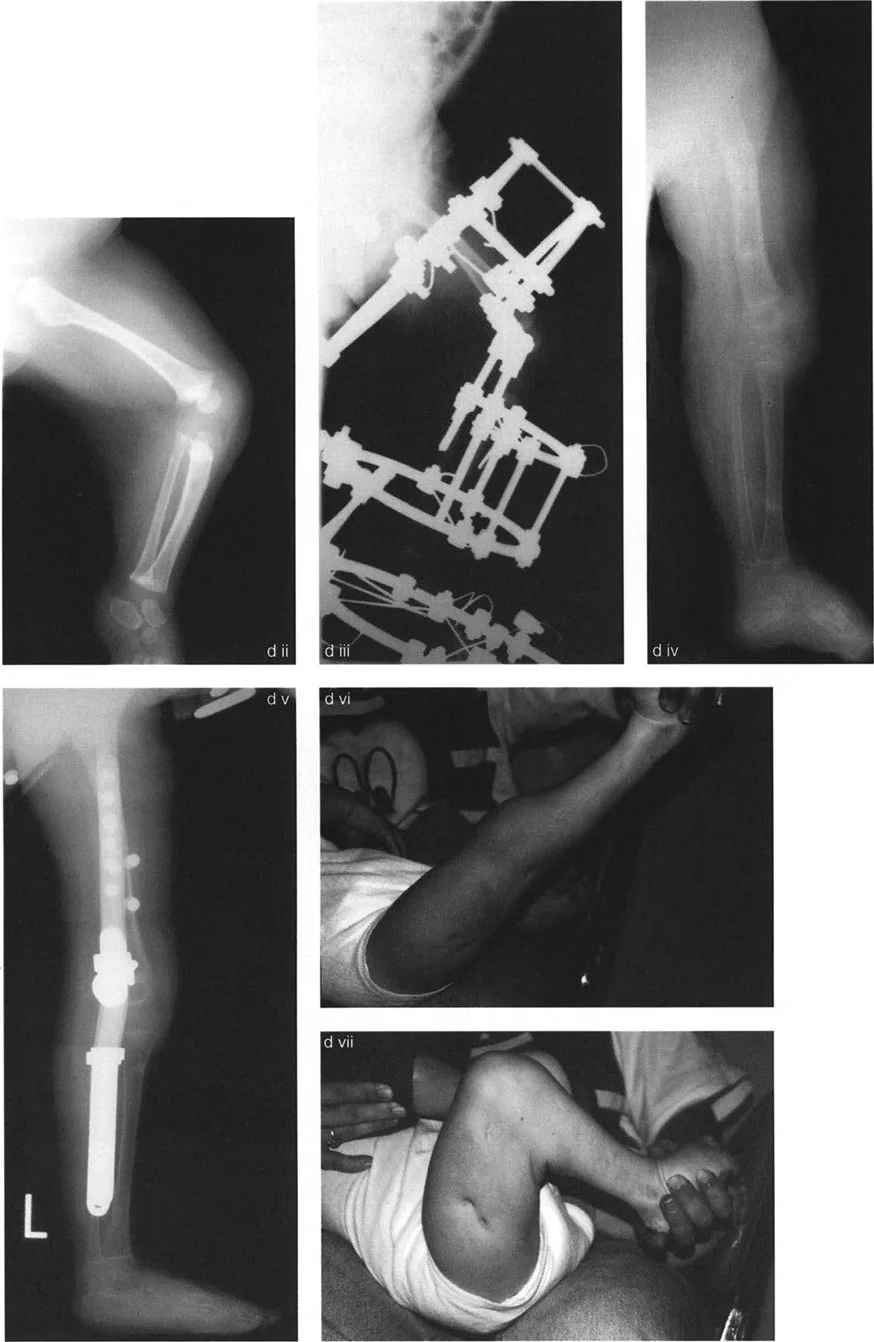

تتضمن جراحة قطع العظم قطع العظم (عادة عظم الفخذ أو الساق) وإعادة تشكيله لتغيير محاذاة المفصل. يمكن أن يكون القطع:

- قطع العظم بالوتد المغلق (Closing Wedge Osteotomy): يتم إزالة جزء صغير من العظم على شكل وتد، ثم تُغلق الفجوة وتُثبت العظام، مما يقصر الجزء المعني ويصحح المحاذاة.

يتم تثبيت العظام بعد القطع باستخدام صفائح ومسامير أو تثبيت خارجي، لضمان التئام العظم في الوضعية الجديدة.

علاج خشونة المفصل أحادي الحجرة الوحشية (LCOA)

ترتبط خشونة الركبة الوحشية غالبًا بالانحراف الأروح (Genu Valgum). يهدف العلاج إلى تحويل الحمل من الحجرة الوحشية المتضررة إلى الحجرة الإنسية السليمة.

- قطع العظم الفخذي البعيد (Distal Femoral Osteotomy - DFO):

- يُعد الخيار الأكثر شيوعًا، حيث يتم عمل قطع في الجزء السفلي من عظم الفخذ لتصحيح الانحراف الأروح.

- مخاطر العصب الشظوي: التصحيح الحاد للانحراف الأروح في الساق قد يؤدي إلى شد العصب الشظوي، مما قد يسبب إصابة العصب أو متلازمة الحيز. قد يُنصح بإجراء تحرير وقائي للعصب الشظوي وقطع اللفافة (Fasciotomy) في التصحيحات الكبيرة، أو استخدام التصحيح التدريجي بالتثبيت الخارجي.

- التصحيح التدريجي: في حالات تحدد الحركة الشديدة أو المعقدة، قد يكون التصحيح التدريجي باستخدام التثبيت الخارجي هو الخيار الأكثر أمانًا.

تصحيح الركبة الارتدادية (Recurvatum Deformity - Hyperextension)

- قطع العظم الانثنائي (Flexion Osteotomy):

- إذا كان التشوه عظميًا (تقوس خلفي)، يتم إجراء قطع عظم انثنائي في عظم الفخذ أو الساق لتصحيح الارتدادية.

- الأستاذ الدكتور محمد هطيف يشدد على أهمية عدم استخدام قطع عظم الفخذ الانثنائي لتصحيح ارتدادية الساق، والعكس صحيح، لتجنب الانزلاق الخلفي أو الأمامي للركبة.

- اعتبارات خاصة: في المرضى الذين يعانون من ضعف عضلي (مثل شلل الأطفال)، قد يحتاج التصحيح إلى فرط تصحيح بسيط (overcorrection) إلى وضعية انثناء لضمان ثبات الركبة ومنع فرط البسط غير المتحكم فيه.